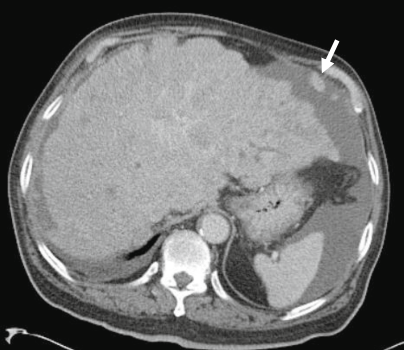

肝周围炎:肝包膜增厚和动脉期强化